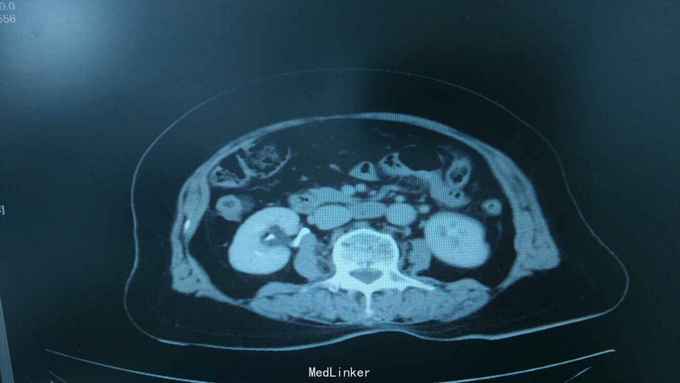

68岁,女性。 主诉:左侧腰痛1年,加重1个月。 病史:1年前无明显诱因出现左侧腰痛,无恶心呕吐,无肉眼血尿。1个月前加重,于外院查泌尿系彩超显示:左肾积液,输尿管显示不清。

查体:腹软,无压痛,左肾区叩击痛(+-),右侧肾区叩击痛(-)。

诊断:双肾盂旁囊肿 治疗:因患者肾盂未明显受压,疼痛症状不明显,等待观察,暂未予处理。

双侧同时出现的病例并不多见,临床只能通过泌尿系统CTU或增强CT加以鉴别,彩超无法区分肾盂积水及盂旁囊肿。